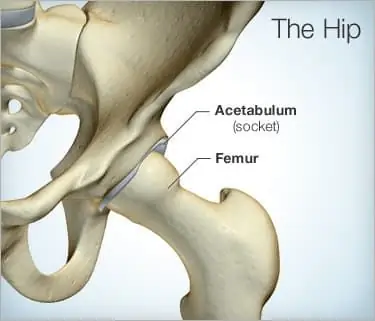

Хотя РА чаще всего поражает суставы рук и запястий, он также может поражать более крупные суставы, такие как бедра, колени и плечи.

Симптомы артрита тазобедренного сустава могут проявиться позже, чем симптомы ревматоидного артрита, поражающего мелкие суставы.

Ра бедра может вызывать такие симптомы, как сильная боль, скованность и отек. При боли в бедре при ревматоидном артрите у вас может быть дискомфорт и скованность в бедре и паху.

Как насчет хирургии тазобедренного сустава?

Операция на тазобедренном суставе является вариантом, когда сильная боль или разрушение сустава вызывают неподвижность.

При более тяжелом течении заболевания может быть рекомендована тотальная замена сустава. Подсчитано, что около 80% пациентов будут иметь хорошие результаты в течение 12-15 лет после замены тазобедренного сустава. Большинство пациентов испытывают небольшую боль после этой операции.